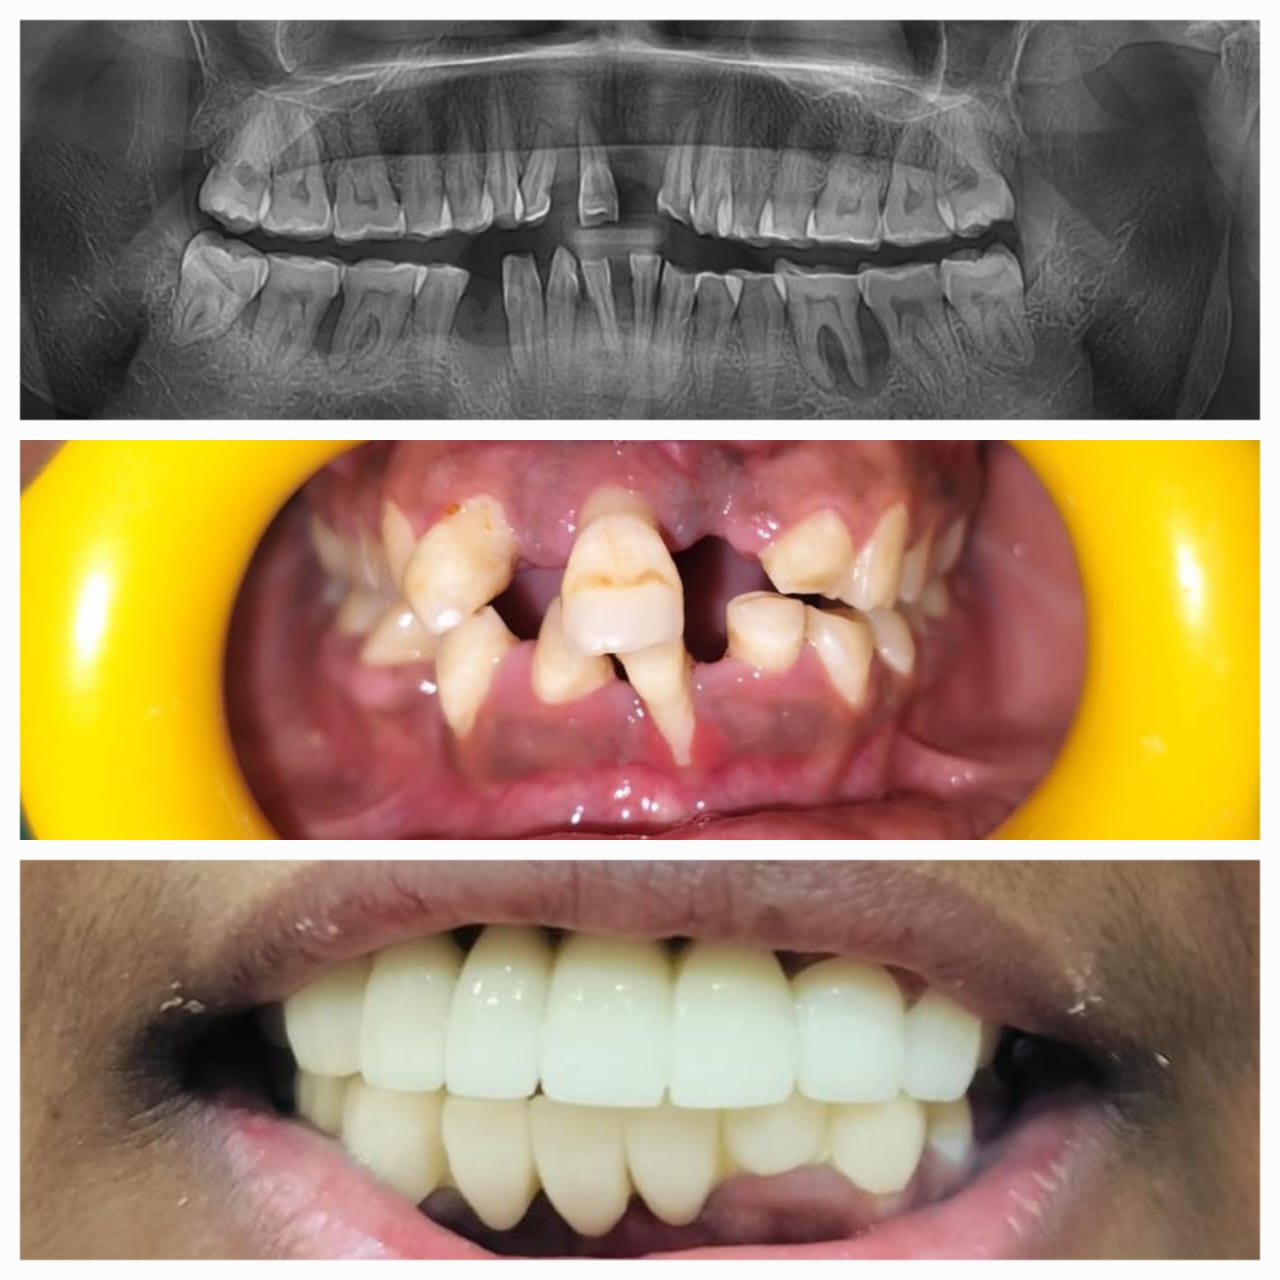

Dental Implants

For replacing a missing tooth or teeth, dental implants are so far the most popular and ideal option. They have had a significant impact on dentistry in the last quarter-century or so....

Gallery